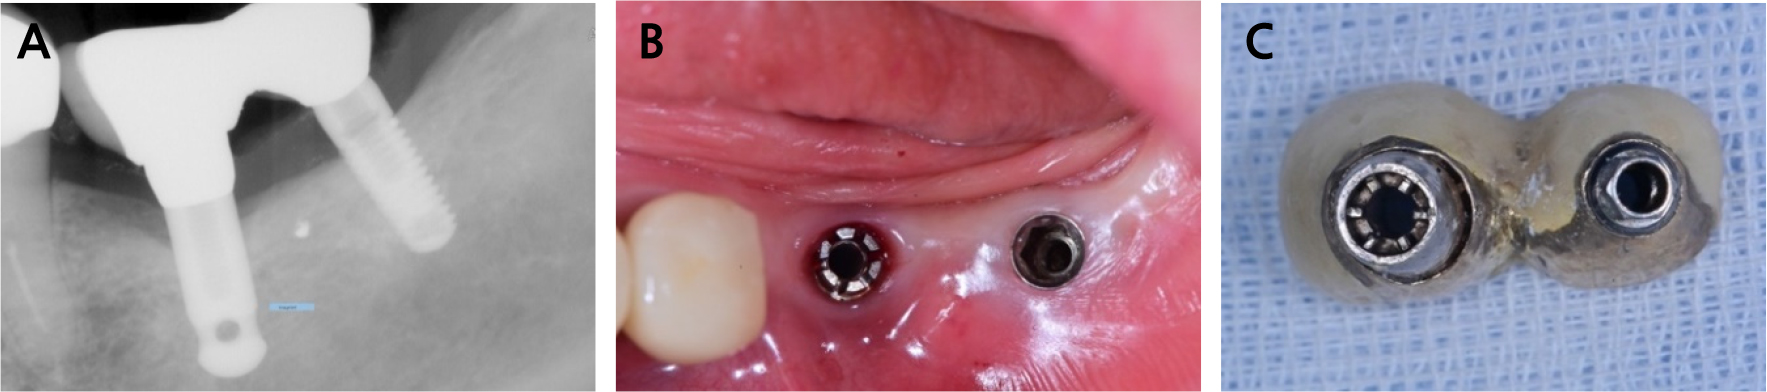

A 73-year-old woman was referred for prosthetic treatment of a maxillary left molar implant at the Department of Oral and Maxillofacial Surgery of the Seoul National University Dental Hospital. Due to pain in the left temporomandibular joint and limited mouth opening, she was receiving treatment with arthrocentesis at the Oral Medicine and Oral and Maxillofacial Surgery department of the same hospital. We found that an implant fixture in the lower left first molar area which was a Zimmer's Spline Φ3.25, and the second molar area which was TSV Φ4.5 from the same company. Periapical radiography showed mild marginal bone loss in the first molar area; however, there was no inflammatory reaction or fixture damage. Osseointegrations of both the implants were intact (Fig. 1A). It was determined from clinical examination that the occlusal dimension of the existing implant prosthesis in the lower left posterior teeth, which is the antagonist, was low. When the existing prosthesis was removed from the oral cavity and evaluated, plaque deposition and wear of fixture connection area of the abutment and some ill-fitting margins of crowns were observed (Fig. 1B and 1C). In order to recreate a harmonious occlusal plane, it was necessary to remake the implant prosthesis. When remaking an implant prosthesis, as a general method, after removing the existing prosthesis, an impression coping suitable for the fixture is connected, and an impression using an impression material such as polyether is obtained. However, components of the implant were not officially imported into the Republic of Korea, thereby making it impossible to take impressions in the traditional way. A domestic company produced a digital scan body (Scanbody Z2, Z6; Dentalrix, Daegu, Korea) compatible with the Zimmer's Spline and TSV (Fig. 2A). Therefore, a new prosthesis had to be fabricated with a digital workflow instead of the traditional method. First of all, after attaching each digital scan body suitable for the fixture, scanning was performed using an intraoral scanner (Trios 3; 3Shape, Copenhagen, Denmark). The implant at the lower left second molar position could be remade using a conventional method by a scan body and ready-made digital laboratory analog. However, the Spline system at the first molar position was not supplied domestically; therefore, it was directly fabricated using digital technology. The connection part that comes into contact with the fixture of the digital scan body is similar to the intaglio on the top of the fixture. Therefore, scanning the digital scan body using an industrial high-resolution, high-precision non-contact image measuring device (Wintek Classic 3020; Wintek Technology, Singapore) was conducted (Fig. 2B and 2C). Data of the top of the fixture was reproduced using the principle of reverse engineering, and CAD software (Solidworks Professional 2019; Dassault Systèmes, Vélizy-Villacoublay, France) was used to merge with the lower part of digital laboratory analog (IZEN implant) data (Fig. 3). A customized digital laboratory analog was fabricated using a three-dimensional (3D) printer (Cara Print 4.0; Kulzer GmbH, Hanau, Germany) and resin (Print Stone Beige; Kulzer GmbH) (Fig. 4A). Based on intraoral scan data, a digital working model was fabricated using a 3D printer (Pro 3D printer; SprintRay, Los Angeles, USA) and resin (S-Plastic model 2.0; Graphy Inc., Seoul, Korea). A ready-made digital laboratory analog for the lower left second molar and a customized digital laboratory analog for the first molar were installed in the digital working model (Fig. 4B). These data were transferred to the CAD software (exocad DentalCAD; exocad GmbH, Darmstadt, Germany) (Fig. 4C). The definitive customized abutments and zirconia crowns were designed using the same software (Fig. 4D and 4E). The definitive prostheses were evaluated for their connection with the implant fixture, occlusion, and aesthetics, and were placed in the patient's mouth (Fig. 5). The patient expressed satisfaction with the functional and esthetically improved prosthetic treatment.

Fig. 1.

Initial condition of implant-restoration complex. (A) periapical radiograph showing mild alveolar bone loss and ill-fitting margins of prostheses, (B) clinical photograph of implants, (C) extraoral photograph of old implant prostheses showing wear, ill-fitting margin, and dental calculus deposition.